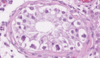

Quelles sont les deux types de cellules retrouvées dans les tubules séminifères ?

- Cellules germinales (90%)

- Cellules de Sertoli